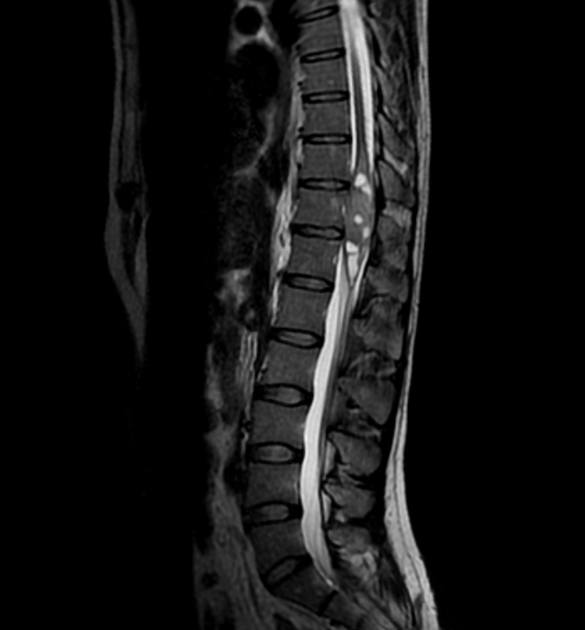

U màng nội tủy

» Thông tin: Nữ giới – 35 tuổi.

» Lâm sàng: Yếu chi dưới.

# U màng nội tủy nhầy nhú (Myxopapillary Ependymoma).